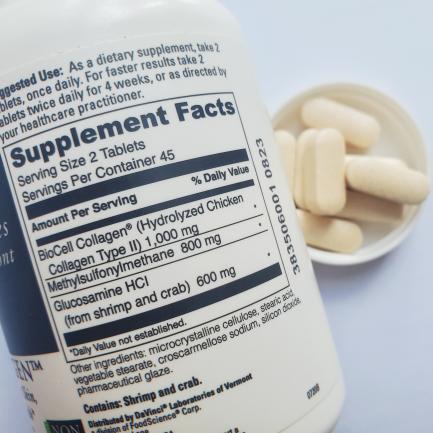

揭秘高效补充胶原蛋白的绝妙方法资讯攻略11-29

揭秘高效补充胶原蛋白的绝妙方法资讯攻略11-29 -